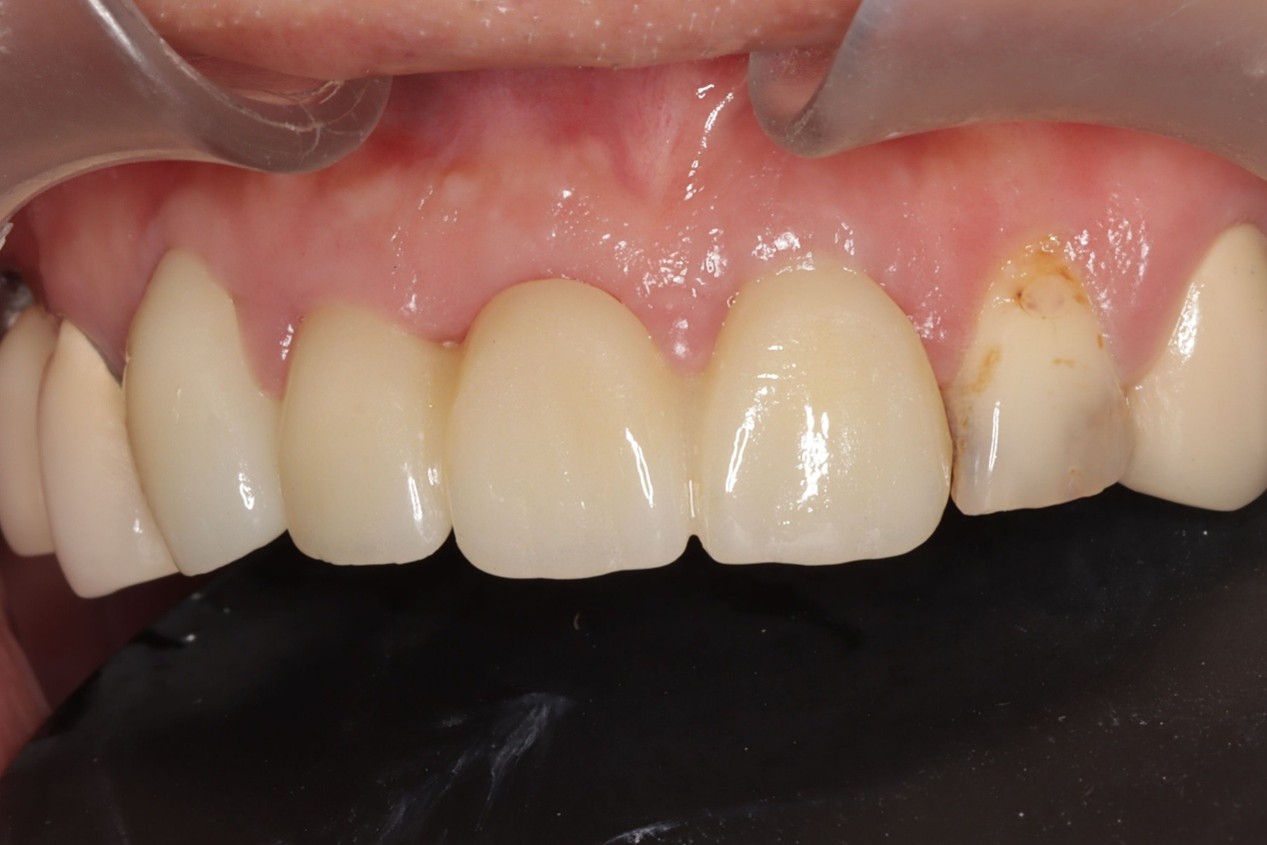

同步反應口腔位置,讓醫師能即時避開血管、神經、縮小創口,達到「真・微創植牙」,加速術後癒合,幫助患者迅速找回笑容自信,讓植牙也能成為無上體驗。

- 創口小癒合快,達到「真・微創植牙」